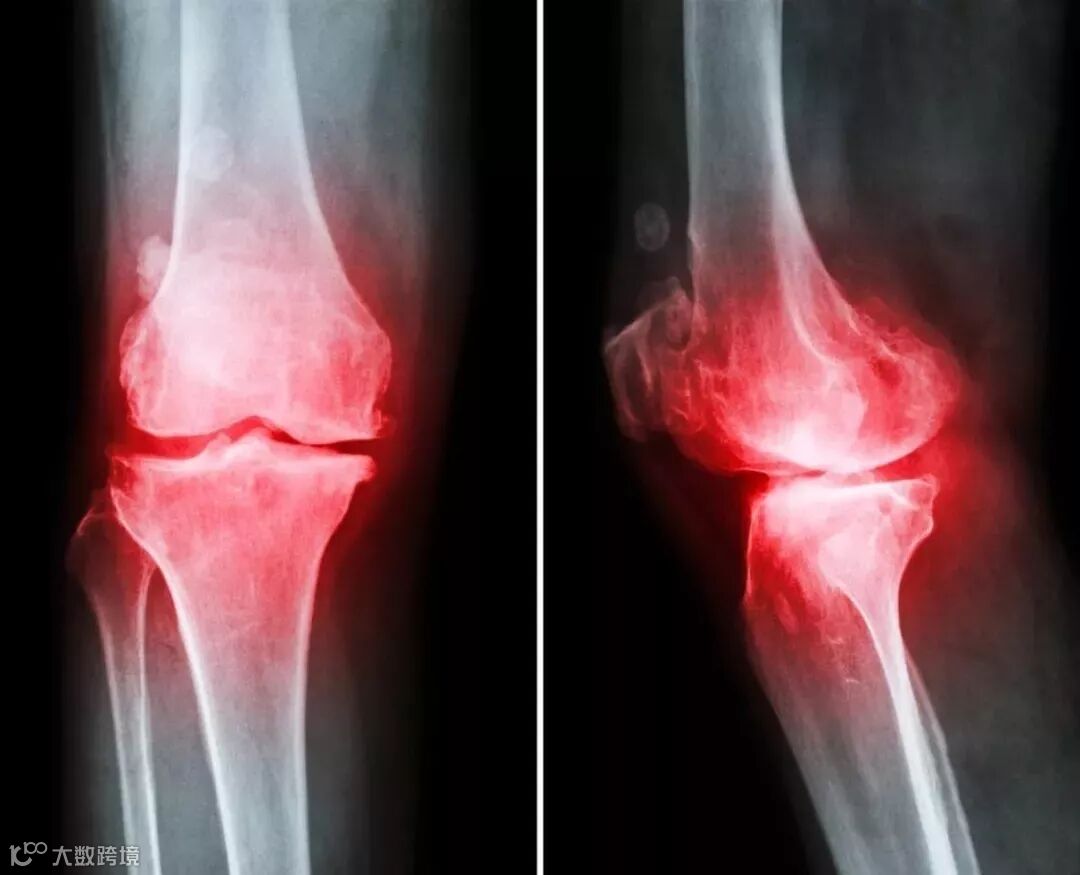

MSCs在炎性关节炎中的应用

类风湿关节炎( rheumatoid arthritis,RA):RA是一种常见的以慢性、对称性进行性滑膜炎为主要表现的炎性关节炎,最终导致骨和软骨破坏。 Jones等在研究中发现,RA患者滑膜MSCs的数目、体外增殖能力以及软骨分化能力均明显下降,提示RA患者的滑膜炎不仅导致骨和软骨破坏,同时损伤了关节固有的软骨再生能力。MSCs兼具软骨分化及免疫调节特性使其成为治疗RA的希望。 研究中发现同种异体来源MSCs和MSCs诱导分化的软骨细胞能够在体外呈剂量依赖性抑制Ⅱ型胶原诱导的RA患者外周血和(或)关节液的T细胞增殖反应,并抑制炎性细胞因子干扰素y和TNF的产生,促进抗炎因子4和IL10的分泌,显示了MSCs治疗RA的应用前景。另一项关于MSCs的体外研究证实,同种异体来源MSCs呈剂量依赖性抑制RA患者外周血T细胞增殖,降低炎性细胞因子干扰素-y、TNFa和L17的分泌,增加抗炎因子Ⅱ10的释放,并促进调节性T细胞亚群的分化;不仅如此,MSCs还能够抑制RA患者成纤维细跑样滑膜细胞炎症细胞因子的释放,减少基质降解酶的产生。

MSCs在骨关节炎中的应用

骨关节炎是一种退行性骨关节疾病,主要表现为关节软骨进行性消失,骨质过度增生。骨关节炎发病与衰老、肥胖、创伤、炎症、遗传等多因素相关。由于关节软骨的再生修复能力有限,临床上又缺乏有效促进软骨修复的治疗方法,目前骨关节炎治疗以减轻症状为主。近年对于MsCs的多向分化潜力及抗炎特性的逐步深入了解,使得MSCs成为有效控制骨关节炎的希望。实验利用两性霉素B注入驴的双侧腕关节诱导骨关节炎模型,造模成功后右腕关节注入悬浮于3m1透明质酸的(1.8~2.3)×10%mlMsCs,腕关节注射相同体积透明质酸作为对照组,实验结果显示MSCs关节腔注射不仅能够改善骨关节炎症状,而且能够延缓骨关节炎的放射学进展,促进关节软骨修复。单次关节腔注射1×10个同种异体来源MSCs治疗兔的骨关节炎模型,治疗后8周放射学及组织学检查显示MSCs治疗能够延缓骨关节炎的进展。

MsCs治疗骨关节炎动物模型的有效性及安全性使其逐步开始进入骨关节炎的临床治疗。 将50例轻中度膝骨关节炎患者分为2组,其中A组接受关节镜手术治疗,B组在关节镜手术同时接受了MSCs局部关节腔注射,随访结果显示关节镜手术联合MSCs治疗能够显著改善骨关节炎的临床转归,提高生活质量。